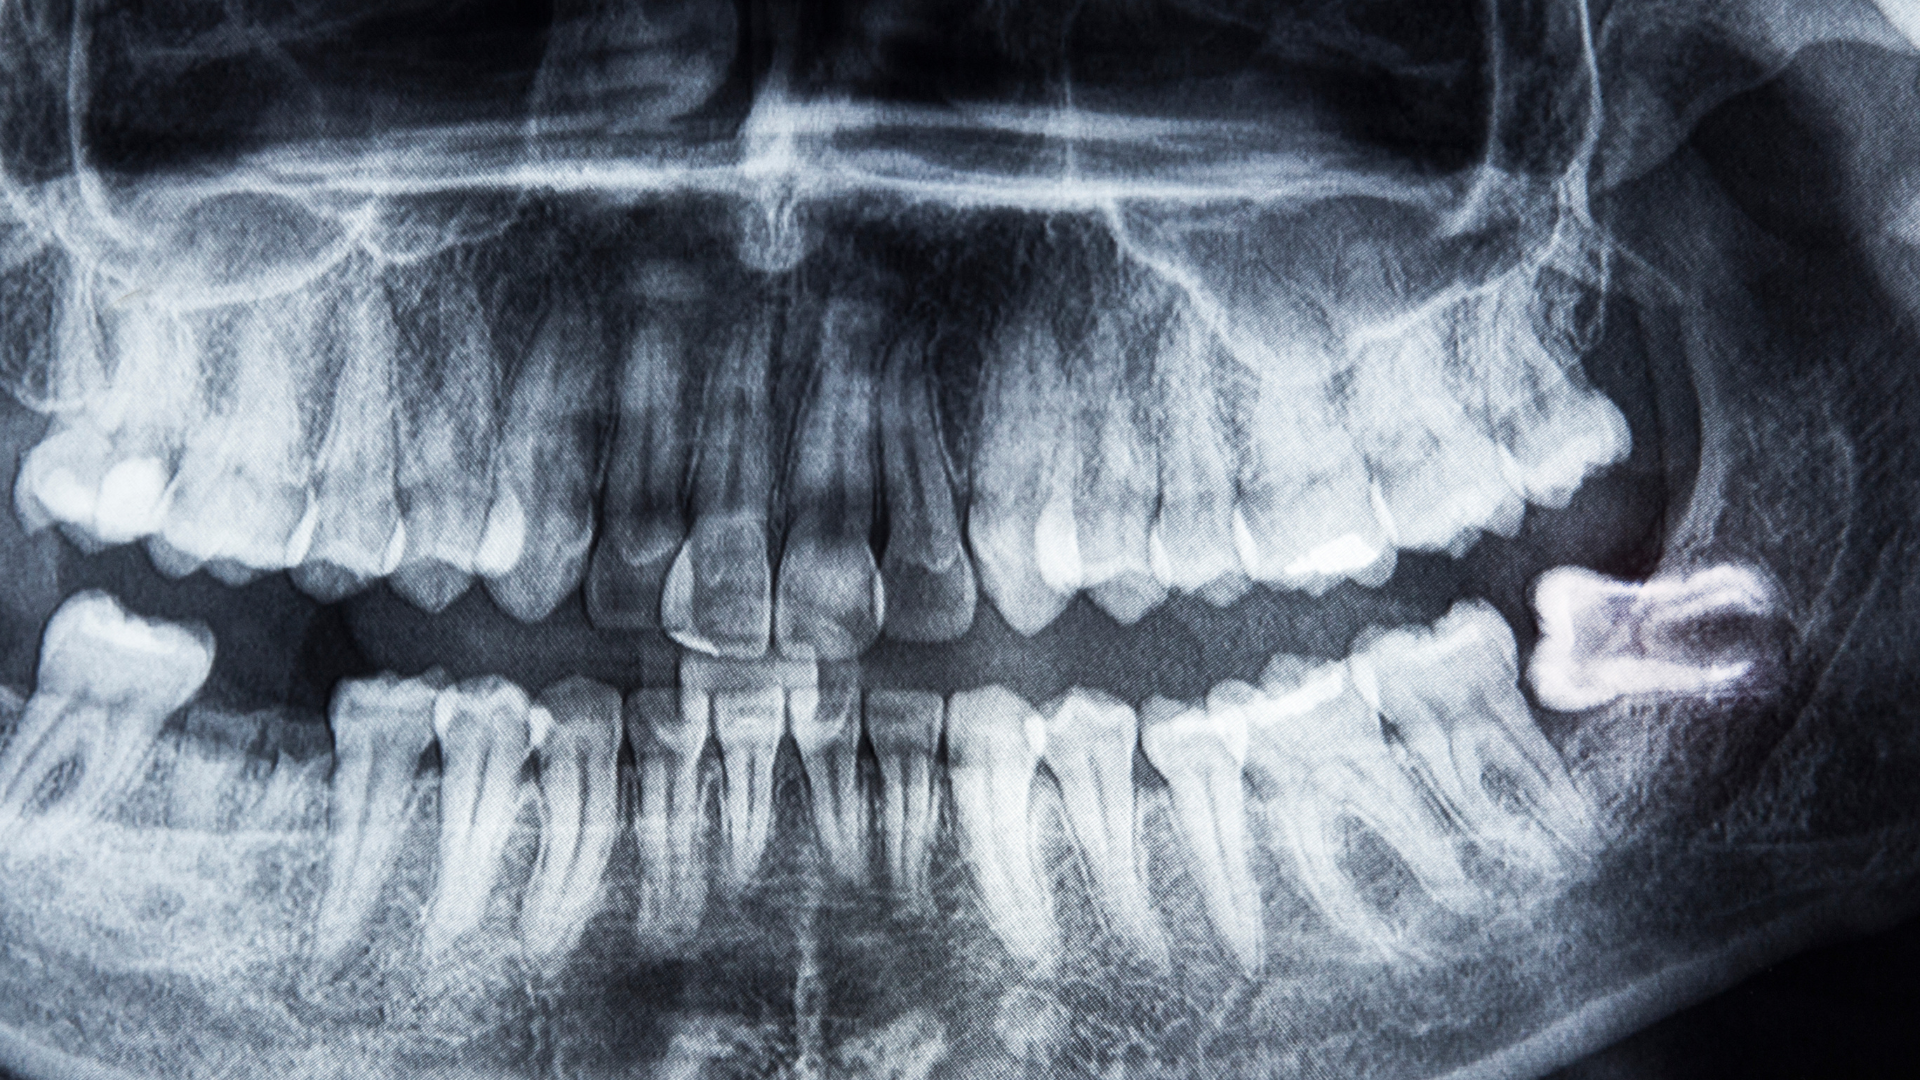

- Có thể nhìn thấy phim X-quang hoặc hình ảnh chụp răng cho thấy răng khôn nghiêng về phía răng kế cận hoặc ra má.

- Chụp phim X-quang (OPG) hoặc CBCT: Để xác định phương hướng mọc, độ sâu, sự tiếp xúc với răng số 7 hoặc dây thần kinh hàm dưới.